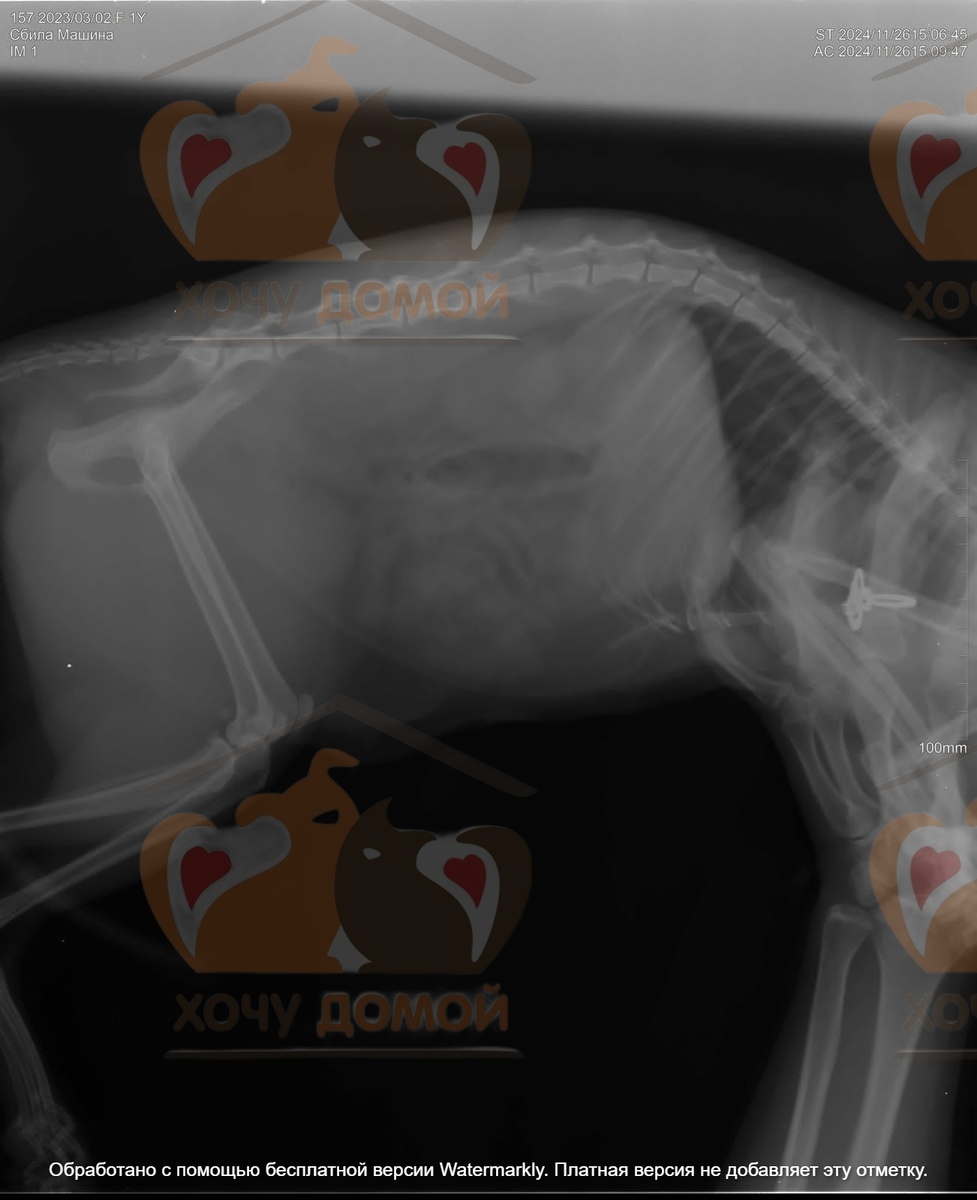

И вот вчера прямо на глазах у людей, когда кошка перебегала дорогу, она попала под машину. В шоке она сначала спряталась за забором, но люди нашли её. Было видно что она сильно пострадала. Тут нужна была неотложная помощь, счет шел на часы. В нашем городе с кошкой были в двух клиниках, к сожалению смогли поставить только диагноз - перелом костей таза. У нас такие сложные операции не делают, к сожалению.

Поэтому пришлось срочно везти бедолагу в соседний город Орёл, в клинику БИО, где уже много лет работает замечательный врач, Кузнецов Д.Г.

Сколько он прооперировал наших животных, не пересчитать, так что кошка в надёжных руках. А нам очень нужна ваша поддержка и помощь с оплатой операции и лечения в стационаре.